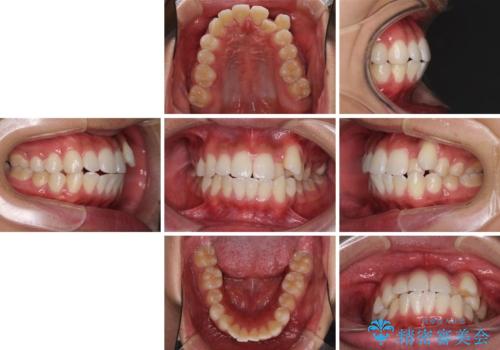

八重歯と奥歯のクロスバイト 上顎骨を拡大してインビザラインで矯正

- 八重歯を気にして来院された患者様です。

八重歯が著しいため、抜歯矯正も視野に入れて検討しましたが、臼歯の咬合関係は正常に近かったので、非抜歯矯正で進める方針としました。

上顎骨の幅が狭く、奥歯がクロスバイトとなっていたため、急速拡大装置を用いて上顎骨を側方拡大し、八重歯を収めるスペースを獲得しつつクロスバイトを改善することとしました。